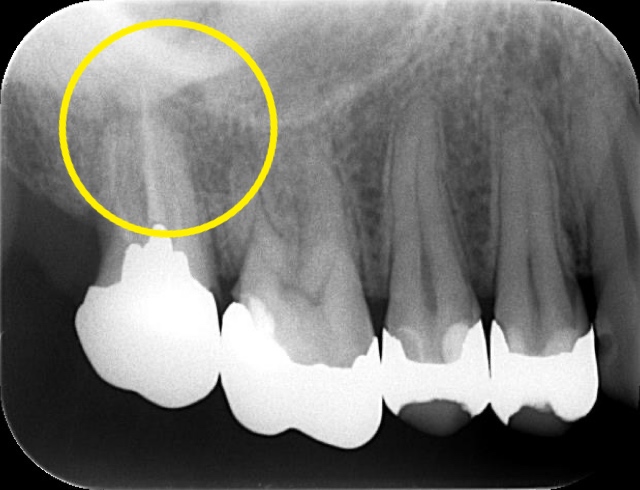

レントゲン画像にあるように、根管治療を行った後、右上の歯のパーフォレーションにはMTAセメントを使用してリペアしました。

(初診時の影がない部分が骨が溶けている様子です)

内側は骨の壁がなくなるほどごそっと溶けていましたが、一目瞭然でバッチリ回復しています!